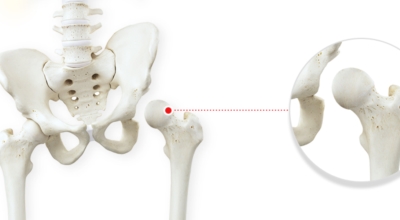

고관절이란 골반을 지탱하는 관절로서 근육과 힘줄로 구성되어 있습니다. 학계에서는 고관절을 엉덩이 관절이라고 부르기도 하며 인체의 하중을 지탱하는 아주 주요한 관절입니다. 각별히 고관절은 우리가 정상적으로 서있거나 움직일 수 있게 만들어주고 달리기, 점프, 무거운 무게를 들 때 최대 체중의 2~10배 가량의 하중을 받기 때문에 적절한 관리가 필요해요. 오늘은 고관절에서 생기게 될 수 있는 고관절 통증 증상에 대하여 알려드릴게요.

고관절염은 고관절에 나타나는 관절염을 말하며 고관절의 연골이 닳게 되면서 뼈와 뼈가 서로 부딪히며 통증을 일으키게 됩니다. 고관절염 초기 증상으로는 사타구니 부위가 불편하게 느껴지며, 무리하면 통증이 생길 수 있다고 하며, 관절염 증상이 심해지면서 사타구니에서 느끼던 통증이 허벅지와 엉덩이 통증으로 이어지기도 하는데, 고관절염 통증 증상으로 초기에는 허리 통증이 나타나 허리 질환과 혼동하기 쉬우며 각별히 척추질환이 있는 사람은 고관절 통증 증상과 마찬가지로 엉덩이, 다리 통증이 동반되기 때문에 훨씬 헷갈리는 경우가 많다고 해요.